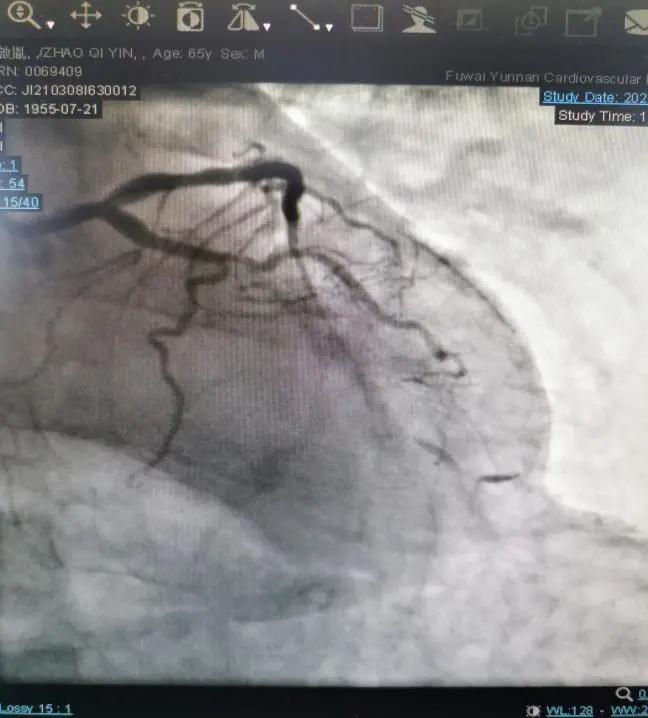

患者多次在外院就诊,冠脉造影检查明确其冠脉血管已经严重钙化,尝试使用药物球囊等技术,术后患者仍发作胸闷胸痛,持续无法缓解,辗转来到云南省阜外医院求诊,入院后收入ICU治疗。冠脉造影显示:患者左、右冠状动脉血管近端严重钙化斑块,远段闭塞,是真正的命悬一线。

病情危重,冠脉病变复杂,齐峰教授勇挑重担,率团队仔细询问病史和阅读冠脉影像,讨论后决定采用冠脉准分子激光斑块消融的方法,来解决患者冠状动脉病变。术中在左冠状动脉反复行激光消蚀术8次后于前降支近中段顺序植入2枚支架。重新疏通了“心路”,患者术后观察了2天无不适症状,顺利出院回家。